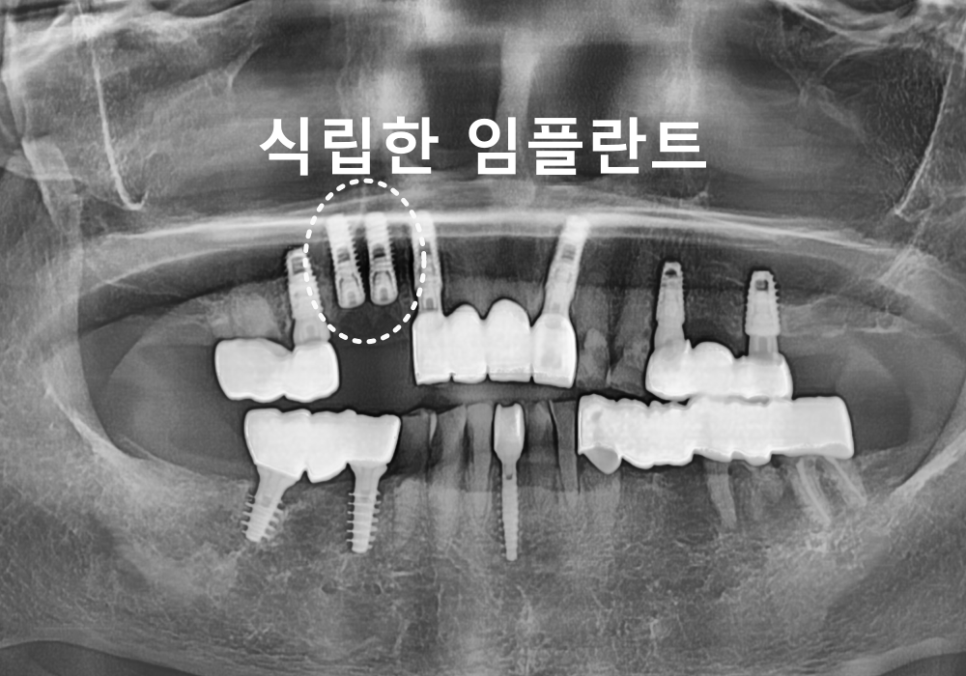

240408

다행히 CT에서 확인했을 때

뼈의 높이와 두께가 비교적 괜찮아

뼈이식 없이 임플란트를

식립할 수 있었습니다.

치유 기간을 거쳐

약 3개월 뒤

최종 보철까지 완성했습니다.

240709